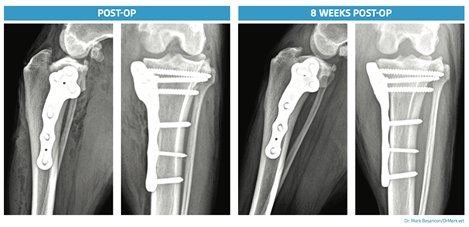

His writing explores topics such as regenerative medicine, orthopedic surgery, and product development, offering valuable insights for both veterinarians and pet owners.